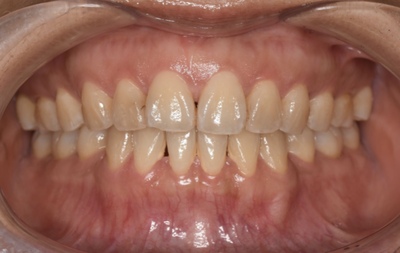

CASE 4

Before

After

基本情報

| 年齢・性別 | 52歳・女性 |

|---|---|

| 主訴 | クリーニングしたい |

| 治療内容 | スケーリング・PMTC |

| 治療期間 | 60分 |

| 治療費 | 約7,000円 |

| リスク・副作用 | 知覚過敏、歯肉退縮 |

| 治療方針 | 歯石とステインを除去して、今後は定期検診でのクリーニングと併せてガムピーリングやホワイトニングを行います。 |

| 担当者所見 | 歯肉の色素沈着が目立つため、ガムピーリングを行いながらホワイトニングを行うことをおすすめします。 |